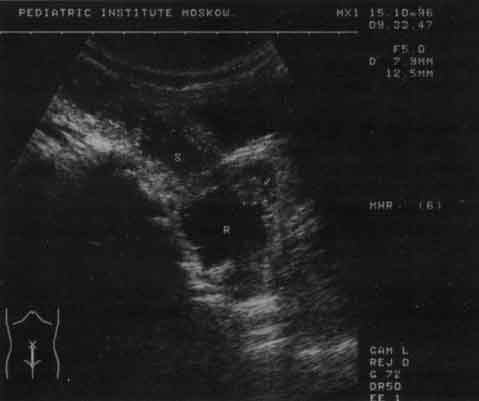

Рис. 10. Эхограмма прямой (R) и сигмовидной (S) кишки (продольный срез). В просвете прямой - полип (обозначен стрелкой).